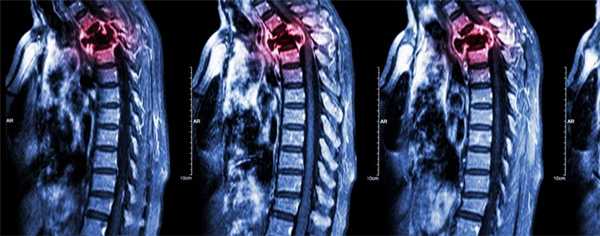

Какие кости поражаются при раке

Принципиально возможно развитие метастаза в любой кости скелета, но чаще всего опухолевые клетки задерживаются в костях с лучшим кровоснабжением, где всегда есть достаточное питание для продолжения неуправляемого деления. Очень редко метастазы образуются в мелких косточках кисти и стопы, но часты в обильно пронизанных сосудистой сетью костях таза, позвонках и ребрах, нередко поражают кости черепа, за исключением лицевого скелета. Наибольшую опасность для пациента несёт опухолевое поражение позвонков и трубчатых костей конечностей, когда в месте деструкции при обычной нагрузке случается перелом, лишающий возможности двигаться, а при патологическом переломе шейного позвонка высока вероятность паралича из-за сдавления спинного мозга отломками разрушенной опухолью кости.

- Чаще всего вторичные отсевы рака возникают в обильно питаемых кровью губчатых костях — позвонках, причём преимущественно в испытывающих высокую нагрузку поясничных и грудных отделах позвоночника.

- Далее по частоте следуют метастазы в костях таза — почти половина всех случаев, типичные локализации — подвздошная и лонные кости.

- синдром сдавления или компрессии спинного мозга осколками сломанного грудного или поясничного позвонка осложняется тяжелыми неврологическими нарушениями ниже зоны повреждения;

- нарушение двигательной активности вплоть до паралича возможно при сдавлении спинного мозга в шейном отделе остеобластическим очагом или повреждении отломками при литическом разрушении.